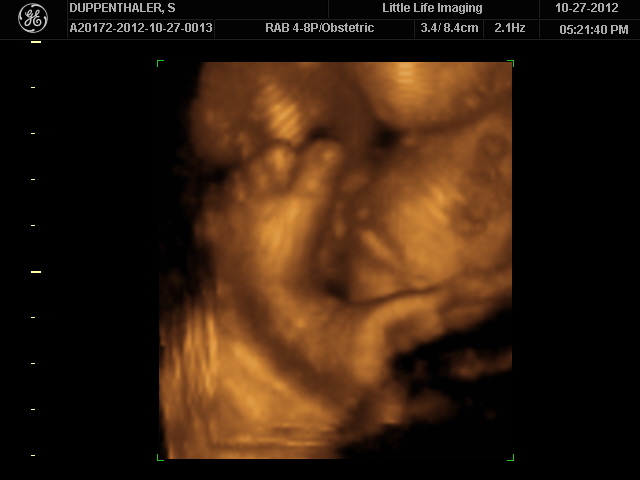

3D sonogram at 32w4d!

Saturday, at 32 weeks and 4 days we went for a 3D/4D sonogram. A couple months ago, Lisa sent me a link to a Living Social deal for this sonogram package for just $47! The same ultrasound costs $180 something dollars at my doctor's office, so this was quite a steal. And, it really makes me wish we had found a deal like this for Addisyn and Alyse's 3D pictures.

The place was really nice and clean, and the tech was very friendly. Little baby gummy was her typical self and spent most of her time hiding from the camera. Either she had her hand in her face, or the placenta would get right in the middle of everything. After spending a few minutes tapping on my belly, having me turn on my side,  and having me press in in specific areas of my belly, we were finally able to get a couple of clear views of her face. And, boy! She sure does look like Alyse. All the way from her cheeks to her toes!

Even though this is number three, it is still just so exciting to see the little babe moving around inside my tummy. Sure, I feel her all the time but to see her WHILE I feel her movements is just absolutely amazing. It's really just something you can't even describe. We watched her yawn and move her hands around. It surely is a little miracle.

Sucking on her wrist

Anyways, "little" Gummy is just like her big sisters and is measuring big in the weight department. 4 pounds and something ounces. Going by weight, it would estimate the due date at December 8, instead of my official due date of December 18. Just one more sign to show that there really is a good chance she will be coming early. Selfishly, coming at the beginning of December would be awesome so that things could settle down before Christmas, but of course we only want that if she's going to be perfectly healthy and ready at that point. Only time will tell.